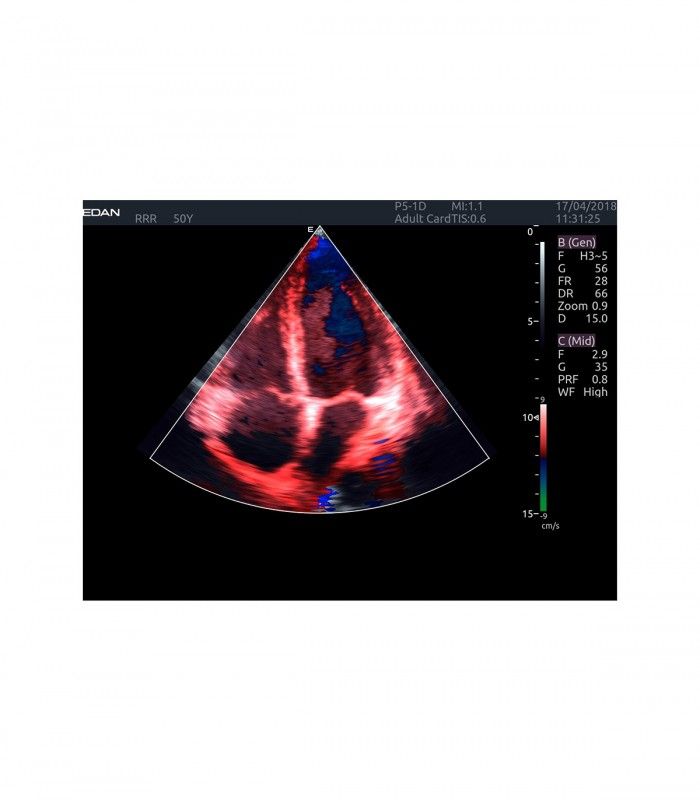

L’AX4 affiche une image claire et précise dans les différents modes grâce à de multiple technologies de traitement de l’image.

L’Imagerie Tissulaire Adaptative (TAI) ajuste automatiquement en temps réel de nombreux paramètres, dès la pose de la sonde sur le patient, afin d’afficher la meilleure qualité d’image, permettant ainsi au praticien de poser un diagnostic plus rapidement.

En mode couleur, les préréglages et le TAI automatique temps réel facilitent l’ajustement des flux.

- Imagerie entièrement automatisée (modes B, couleur, doppler, M)

- Dopplers pulsé PW, continu CW, énergie (ou puissance) PDI et DPDI